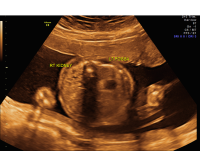

Unilateral renal agenesis axial

Renal agenesis refers to the absence of one or both kidneys. Unilateral renal agenesis is fairly common and affects one in 1,000 births, whereas bilateral renal agenesis occurs in only about one in 4,000 to 7,000 pregnancies.